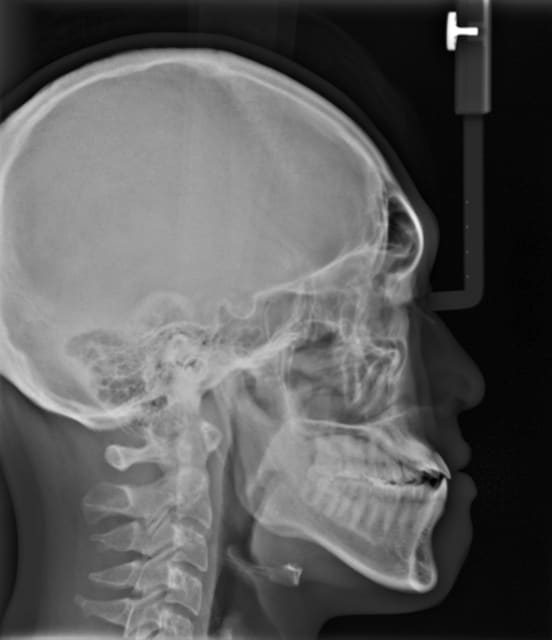

Patient asiatique, 25 ans, consulte car il veut corriger son crossbite bite antérieur localisé aux latérales et son crossbite secteur 2/3. Il aimerait également corriger son apparence générale, son profil notamment.

Classe III squelettique et dentaire.

Ci joints photos, ceph, modeles.

Le mesh utilisé ici est un asian mesh.

Par ailleurs ce n'est pas une prévision finale du traitement, c'est une aide au dignostic à base de normes préétablies de positionnement des points de repères.